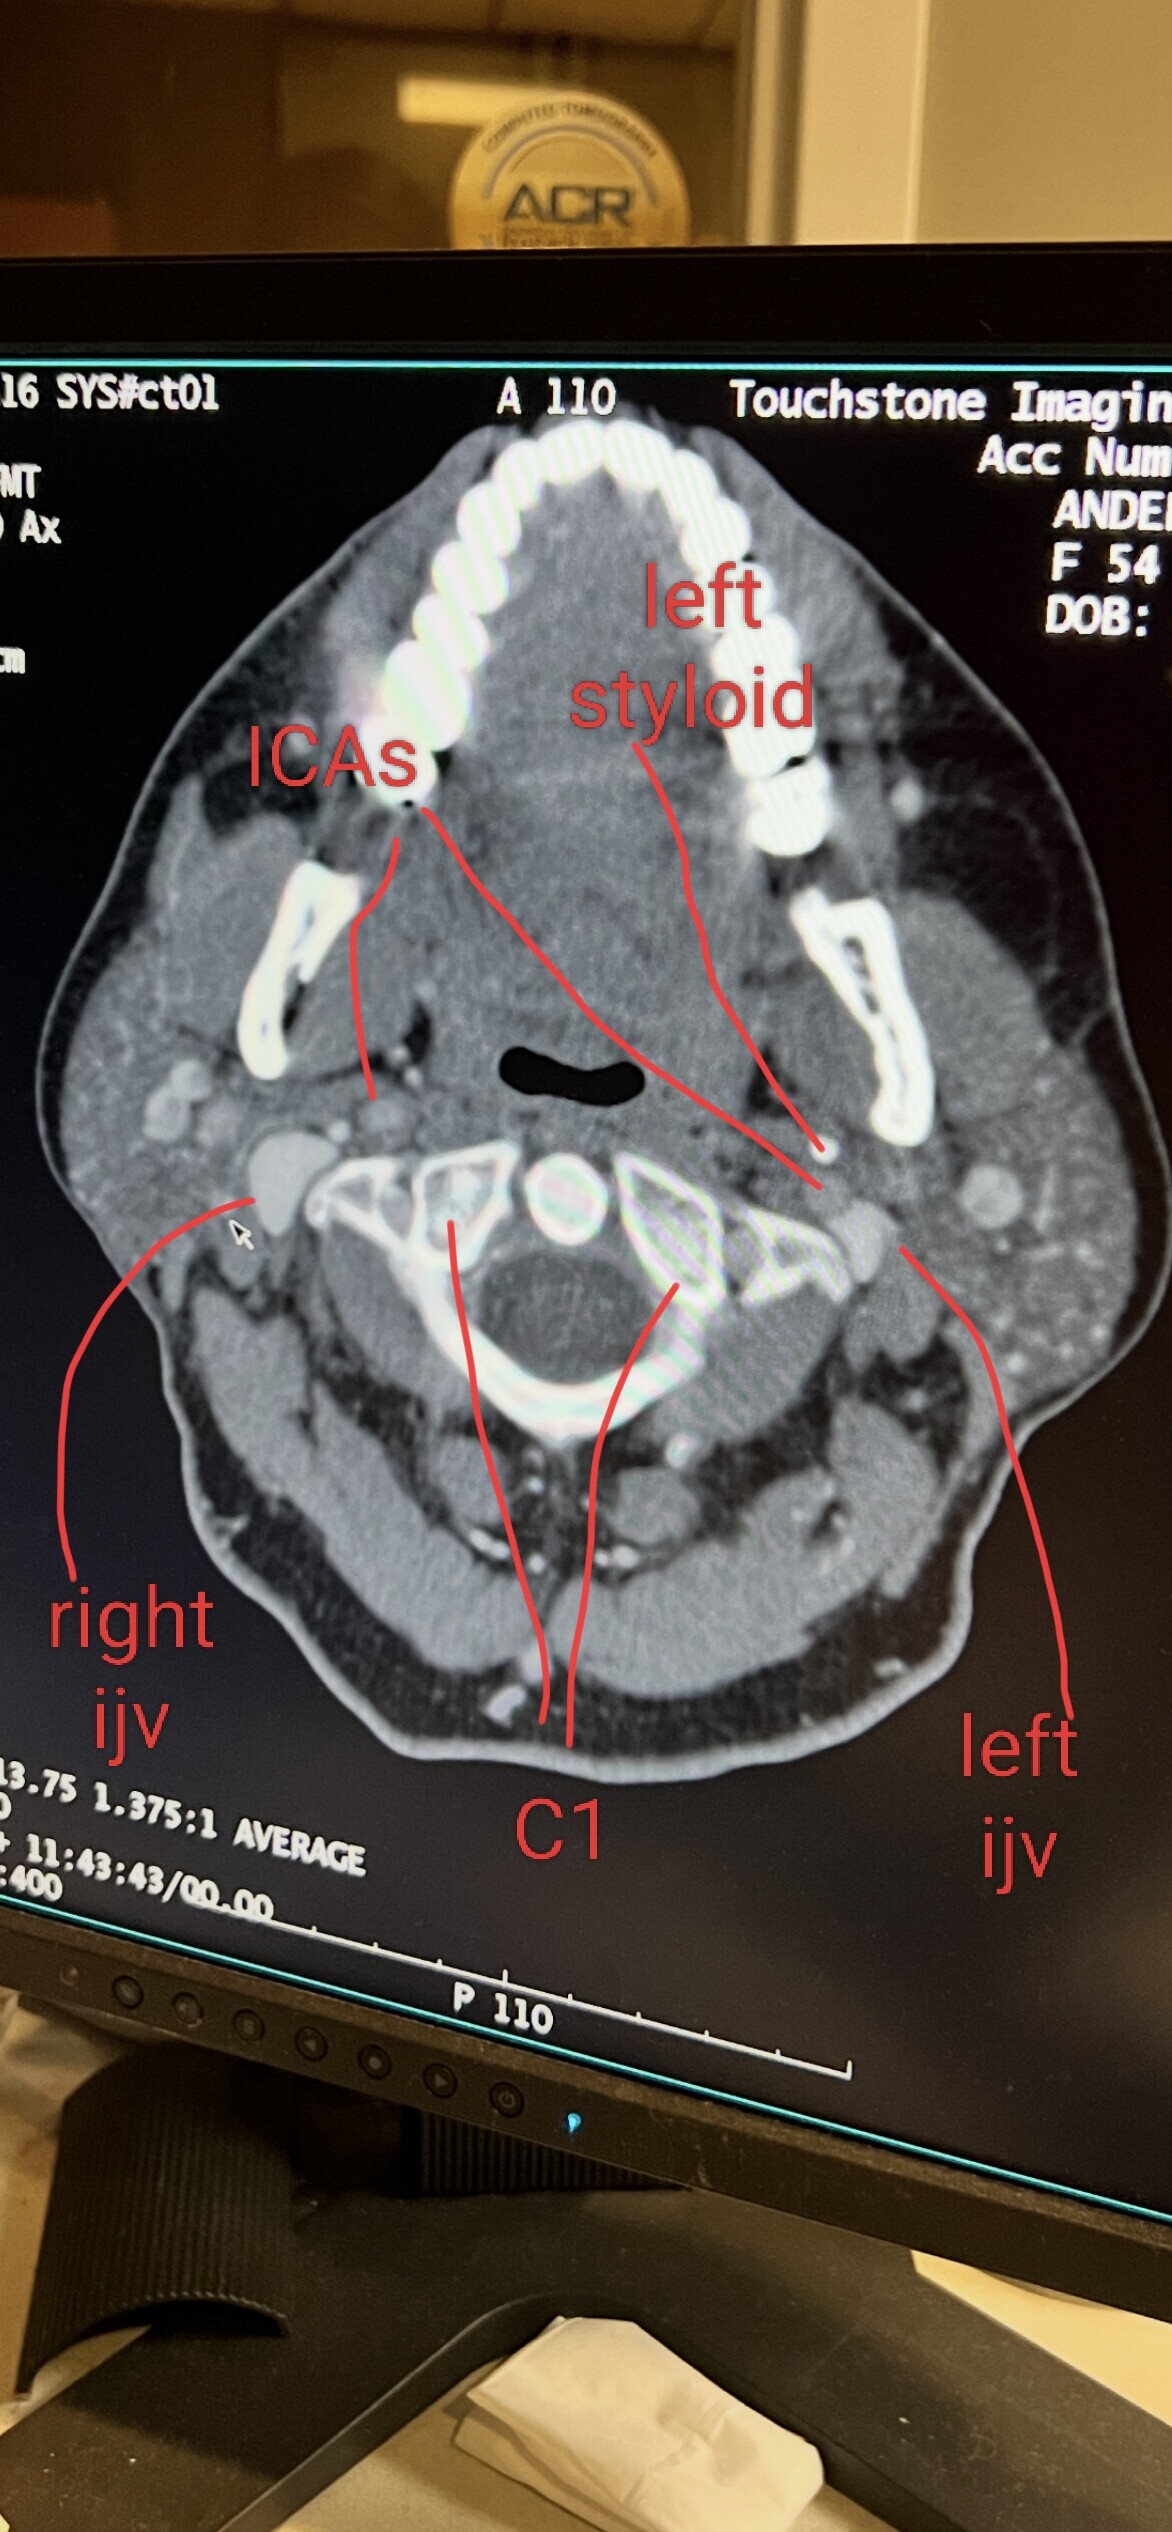

@Minh2025 see attached annotated imaging.

Both your IJVs are compressed against the wings of your C1 tranverse process.Your styloids aren’t causing any compression (at least at this specific slice). C1 shave on both sides could help open the IJVs up. We’ll have to see a 3D reconstruction to see the full lengths of your stylohyoid ligaments.

Your left ICA is pushed up against your left IJV which I don’t see often. Not sure if this is contributing anything or not. I’d say stay away from atlas adjustments. Any temporary loosening or shifting of C1/C2 could cause temporary flare ups of your symptoms. Your vagus nerves may be compressed between your IJVs and C1 as well.